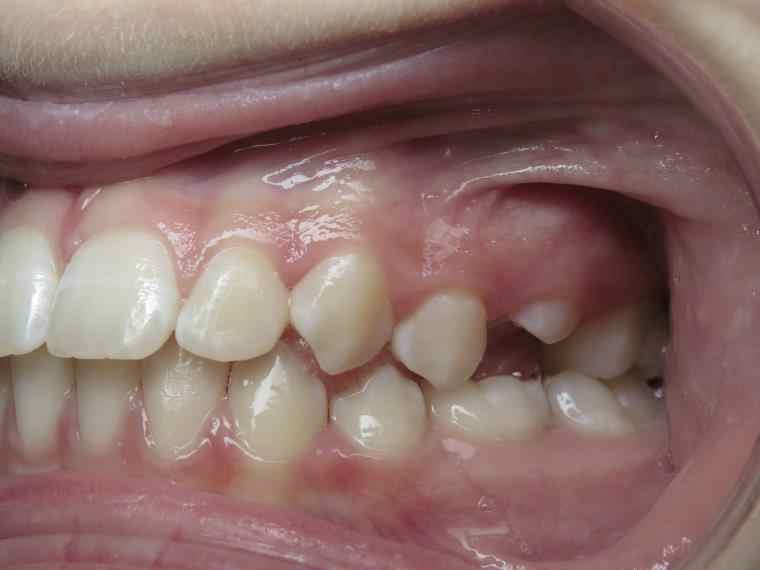

surveillance évolution de la dentition pendant 5 ans

appareillage multibagues traitement en cours

bilan début et en cours de traitement